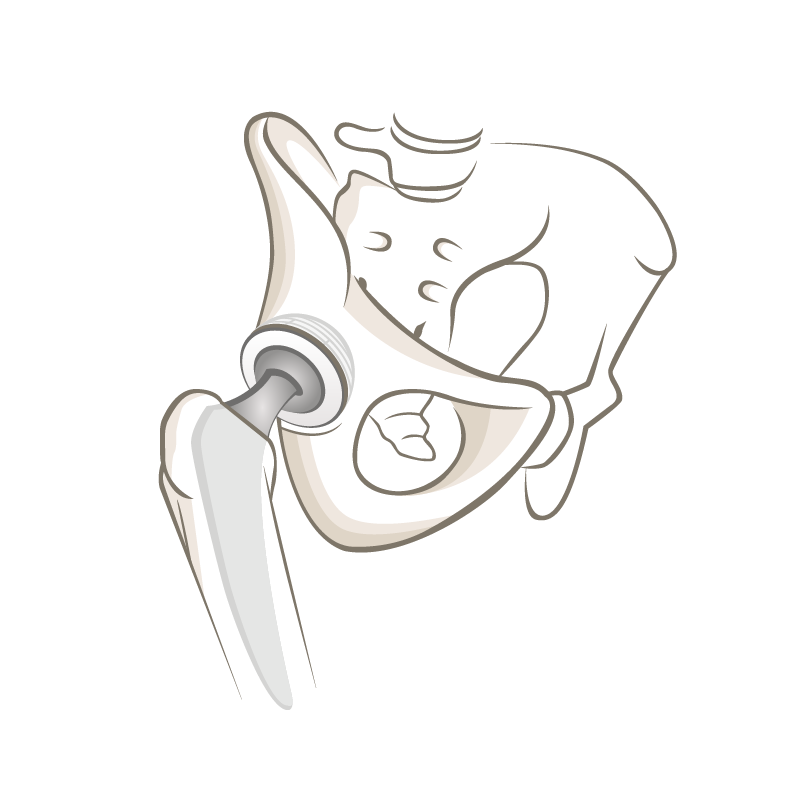

Die Entwicklung der Hüfttotalendoprothese: Vom Jahrhunderteingriff zur modernen Orthopädie

Dr. Philipp Neidenbach berichtet über die Entwicklung der Endoprothetik des Hüfgelenkes. Die Hüfttotalendoprothese revolutionierte seit den 1960er-Jahren die Behandlung der schweren Hüftarthrose, so dass die Implantation der Hüftprothese bereits 2007 als «Operation des Jahrhunderts» gefeiert wurde. Die stete Weiterentwicklung der Operationstechniken und Materialien der Implantate hat dazu geführt, dass Patienten schmerzfrei mobil sein können.

Die Langzeitresultate sind, im Vergleich zu vielen anderen chirurgischen Verfahren, aussergewöhnlich gut. Dr. Philipp Neidenbach gibt in seinem Beitrag einen spannenden Einblick in die Evolution der Hüftendoprothetik, deren Möglichkeiten und Grenzen.